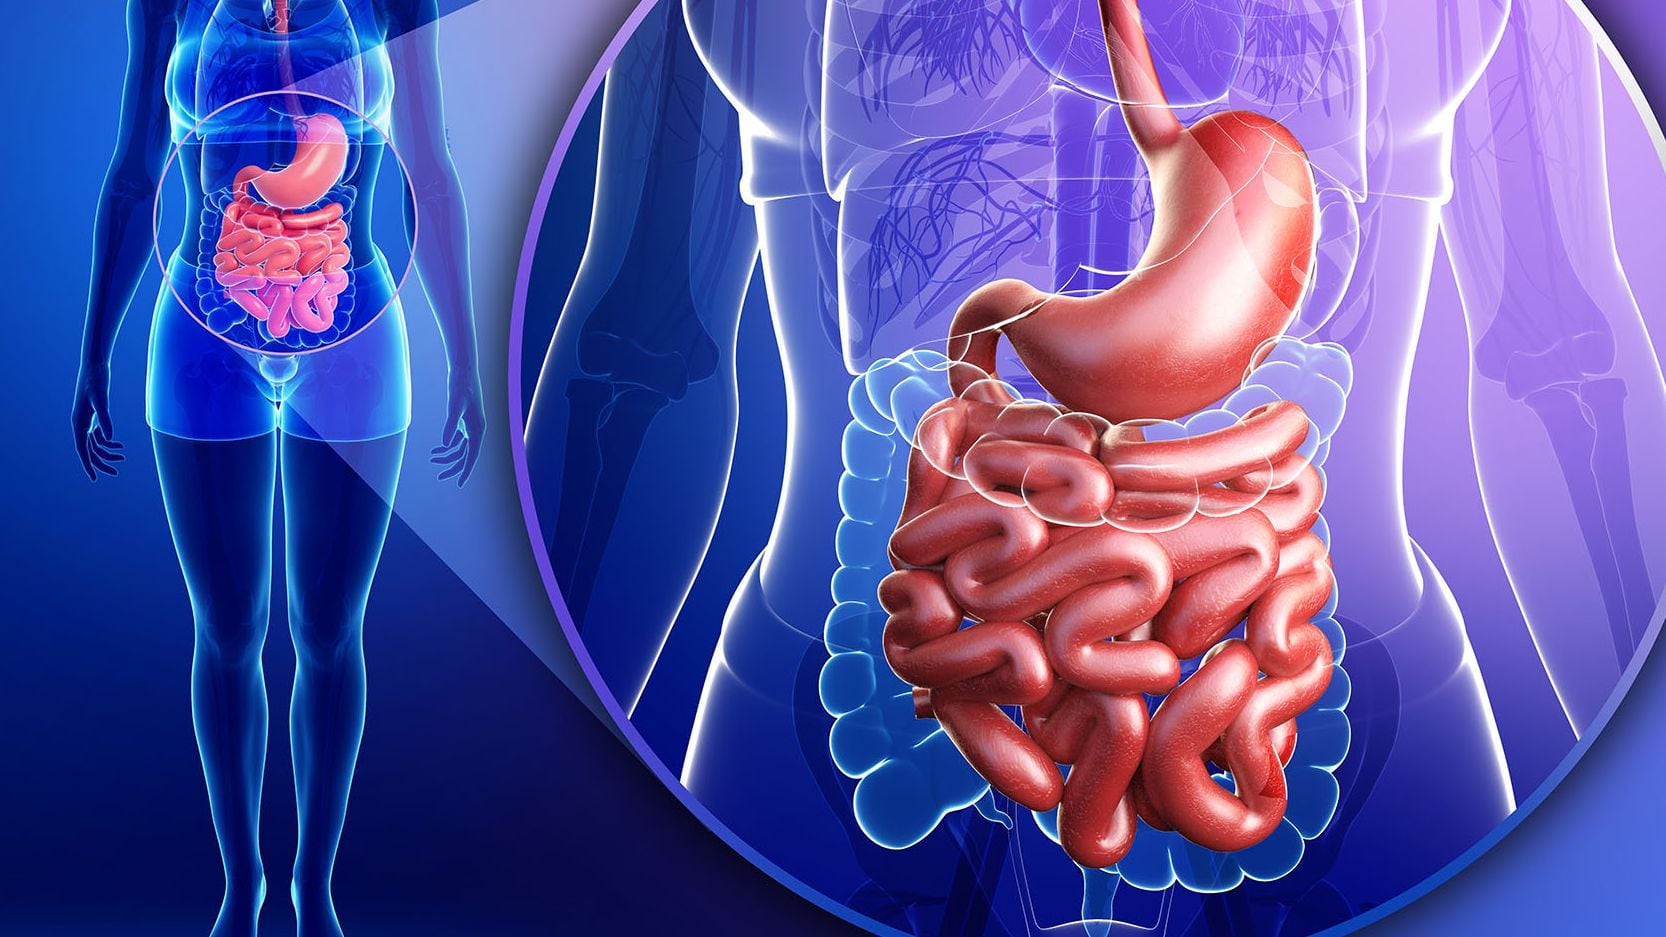

Lo cierto es que, un estudio científico publicado en la revista Nanomedicine: Nanotechnology, Biology and Medicine realizado en organoides por expertos de la Facultad de Ingeniería de la Universidad de Tufts (Estados Unidos), encontró que los microplásticos “pueden ingresar a la cadena alimentaria y dirigirse al intestino humano”, generando, en algunos casos, “la secreción de moléculas inflamatorias relacionadas con la enfermedad inflamatoria intestinal humana”. Estas últimas son patologías autoinmunes que implican inflamación de los tejidos del tracto digestivo por un tiempo prolongado -crónico-.

“Sabemos que las partículas de plástico están en todas partes en el medio ambiente y se han encontrado en los intestinos humanos y otros tejidos, como la sangre, e incluso en el cerebro y la placenta”, explicó Ying Chen, uno de los autores de la investigación. Al tiempo que resaltó que las células epiteliales, que recubren el interior del intestino, podrían “absorber los microplásticos más diminutos, mientras que las células M (NdeR: que actúan en la respuesta inmunológica, entre otros procesos) absorberían y transportarían micropartículas más grandes al tejido intestinal”, de este modo se produciría un daño en el revestimiento intestinal que “puede implicar un potencial en la generación de lesiones intestinales”.

En 2022, la OMS publicó un informe sobre los efectos de los microplásticos en la salud humana y detalló que “los estudios epidemiológicos entre trabajadores de la industria sugieren que la exposición a concentraciones elevadas de microplásticos en el aire, como el polvo de cloruro de polivinilo (PVC) y nailon, usados en construcción, puede provocar daños en las vías respiratorias”. Mientras que al encontrarse en alimentos, si se extrapolan los datos de otras partículas microscópicas insolubles, se registra una “generación de radicales libres y la respuesta inflamatoria”.